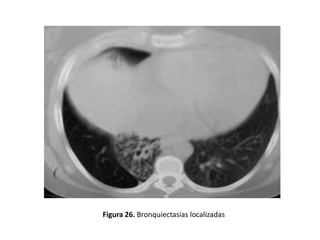

• Según el grado de extensión

– Localizada

• Afectación segmentaria, unilobar o bilobar (en el caso

de dos lóbulos contiguos anatómicamente) y suelen ser

debidas a obstrucción de la vía aérea (extrínseca o

intrínseca), infecciones, secuestro pulmonar, etc. (figura

26).

Figura 26. Bronquiectasias localizadas